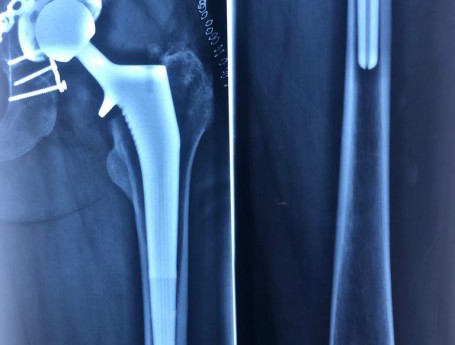

Revision Total Hip Arthroplasty Femoral Stem